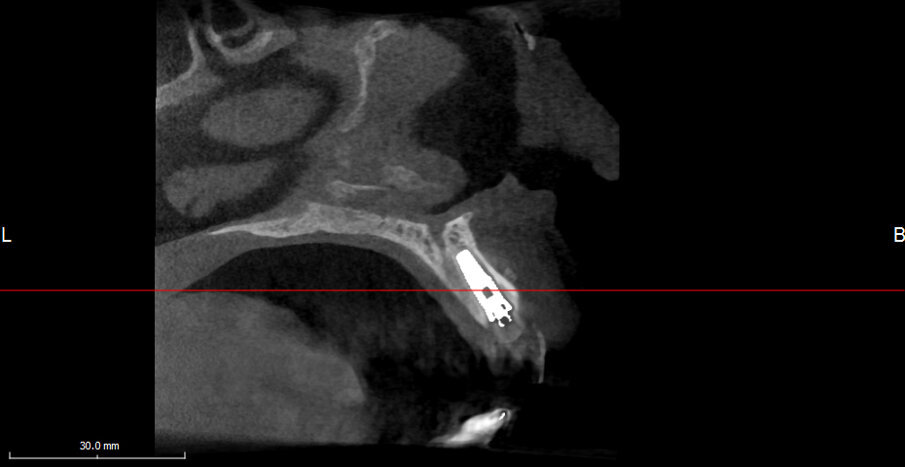

The intraoral scan is imported into CAD software and transformed into a virtual master model without the tooth to be extracted and a separate STL shape of the ideal CAD-designed tooth (Fig. 9). Now there is the opportunity for 3D evaluation of the dimensional relation between the new tooth and the soft tissue before extraction. In the current case, the tooth involved had not been extracted and a CBCT scan was performed (X-Mind trium, ACTEON; 110 x 80 mm field of view; 0.15 mm voxel size) for further investigation and treatment planning. In the AIS 3D App software that comes with the CBCT X-Mind trium device, STL files can be matched and aligned with the 3D bone volume, thus giving the opportunity to plan the future implant position taking into account the shape and position of the future crown (Figs. 10a & b). In accordance with the prosthetic procedure preferred, cemented versus screw-retained, CAD/CAM-fabricated versus manual layering and the type of material to be used, all the information for the final treatment plan is available, on which decisions can be made regarding GBR, connective tissue graft and timing of implant loading.

Analysing the CBCT scan

It became evident that the short-rooted tooth could be extracted without compromising the buccal bone, and that there was sufficient bone volume and quality to obtain good primary stability of the implant. Thanks to the AIS 3D App software, this information can be visualised using the bone density tool and linear measures tool (Fig. 10c) and represented in a graphic or according to a coloured scale. The presence of the nasopalatine duct prohibited ideal palatal positioning of the implant, and if the implant were to be placed flush with the palatal alveolar bone, this would have resulted in a 1.5–2.0 mm high exposure of the implant collar on the buccal aspect (Fig. 11b). This information, combined with the aesthetic analysis, led to the decision to place the implant in that position and to augment the buccal bone volume with a contemporaneous GBR procedure, thus also providing for major soft tissue support. As often described in the literature, it is to be expected that in some measure the implant will deviate buccally2–4 from the original planning because of the major mechanical resistance of the palatal plate. The author’s team prefers whenever possible screw-retained solutions. Several production centres are capable of milling angulated screw access holes in cobalt-chromium abutments of up to 25°,5 which is a range that covers most cases in daily practice. It can be easily checked in the implant planning software whether the future access hole will exit on the palatal aspect of the tooth, either by angulating the implant extension tool or by choosing a virtual abutment from the library. Confirming being in the safety range from this point of view allowed for an approach that foresaw the implant in native bone without the necessity for major GBR on the apical aspect of the implant. Knowing that a flap needed to be raised to facilitate the marginal tissue augmentation, it was decided to use a surgical guide (Figs. 11c) for only the first drill to determine with precision the position and angulation of the osteotomy that would be performed freehand thereafter. In order to limit surgery time and eliminate unpredictable factors inherent in immediate loading, a removable temporary prosthetic tooth was produced in advance.

Innovative technologies enable extremely accurate diagnosis and treatment planning. Affordable high-quality CBCT has profoundly changed our profession. In the current case, the detailed X-Mind trium 3D images allowed for planning and performing implant placement in the optimal mesiodistal position. Correct distances to the lateral incisor and the nasopalatine duct were obtained. Final choices will always remain related to the experience, skills and equipment of the performing team. After collecting all of the necessary information and knowing what technology can provide, it is possible that one team will opt for GBR and monolithic crowns, where another might try to minimise the invasiveness of surgery and employ innovative milling strategies to deliver a predictable, beautiful solution. In the actual challenging buccopalatal dimension, the implant was perfectly planned and guided into to the centre of the native bone. Guided bone regeneration was limited to the minimum and minor buccal exposure of the implant was predicted. Reviewing the case described above, the fact that bone volume could be matched with the dental preoperative situation and the CAD virtual wax-up made the whole procedure, from extraction to final restoration, highly predictable. Bone volume, bone quality, extent of GBR indicated and the type of prosthodontic solution were all known before starting treatment thanks to the implant planning with the AIS 3D App software.